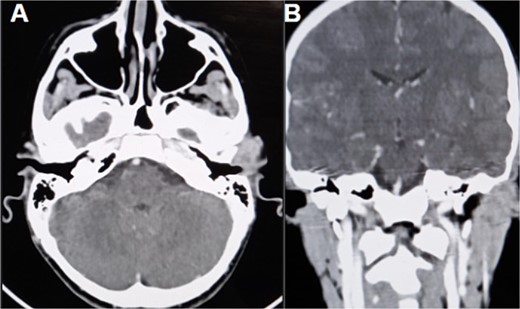

The CT scan showed an ill-defined, subcutaneous granuloma with heterogeneous enhancement, measuring 14.6 × 14.2 mm. The mass caused a smooth scalloping of the temporal bone without any locoregional spread or distant metastasis. Regional lymph nodes were free of tumors (Fig. 1). The patient underwent a complete surgical resection, and the mass was sent to our department for histological examination. Morphologically, the tumor showed a multinodular architecture with central areas of necrosis mimicking a granulomatous process. Tumor cells had a polygonal or spindled shape with eosinophilic cytoplasm, vesicular chromatin, and conspicuous nucleoli (Fig. 2). The stroma was myxoid, and some dystrophic calcifications were noted.

CT scan (A) axial section shows an ill-defined subcutaneous granulomatous process. (B) Coronal section of the process causing scalloping of the temporal bone.